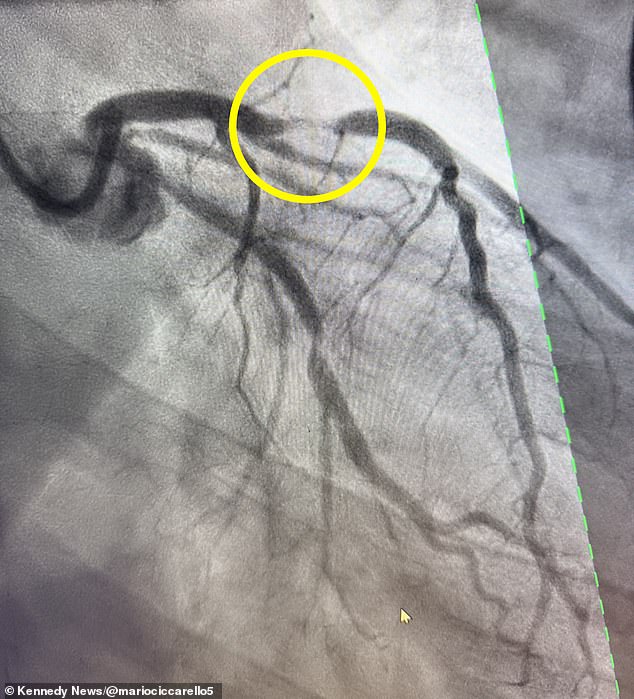

Mario Ciccarello, a 34-year-old warehouse worker and avid ultra-marathon runner, believed his chest pain was a temporary reaction to spicy Mexican food. This assumption nearly cost him his life. After a workout in February, Ciccarello experienced sharp chest pain radiating to his shoulder and arm—classic signs of a heart attack. His fitness and age led him to dismiss the symptoms as a temporary issue, but the pain intensified hours later, leaving him breathless and desperate. 'I looked at my son sleeping and wondered if it was the last time I was going to see him,' he later recalled. His resting heart rate surged to 112 beats per minute, signaling severe cardiac distress. Despite his physical fitness, Ciccarello's condition was far from benign. He had suffered a 95 percent blockage in his left anterior descending (LAD) artery, a blockage that doctors classified as a 'widow-maker' heart attack. This term refers to the high mortality rate associated with the LAD artery, which supplies critical blood to the heart's pumping chamber. Only 12 percent of patients survive such events without immediate intervention.

The medical response was swift but precarious. Emergency teams inserted two stents into Ciccarello's artery, restoring blood flow and saving his life. He now takes blood thinners and undergoes genetic testing while advocating online for younger people to recognize heart attack symptoms. Chest pain, shortness of breath, dizziness, and nausea are red flags, regardless of age or fitness level. 'Every minute you wait causes more damage to your heart,' he emphasizes. His story underscores a broader public health challenge: the need for early education and access to care.